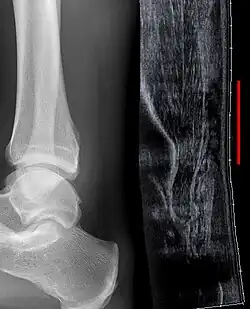

Achillessehnenruptur in der Sonographie: Kontinuitätsunterbrechung über mehrere Zentimeter (rote Linie). Röntgenbild daneben zum Ausschluss knöcherner Verletzungen.

Klinisch findet sich bei ganz frischen Rupturen meist eine tastbare Lücke, am häufigsten wenige Zentimeter oberhalb des Ansatzes am Fersenbein (Calcaneus). Nach einiger Zeit ist der Bereich blutunterlaufen und geschwollen. Gehen auf den Zehenspitzen ist nicht mehr möglich. In Rückenlage kann der Fuß auch nicht mehr plantar (fußsohlenwärts) bewegt werden. Eine Restfunktion kann durch die Sehne des M. tibialis posterior und durch die langen Zehenbeuger simuliert werden. Eine weitere Untersuchung stellt der Thompson-Test dar: Der Patient liegt auf dem Bauch, die Füße hängen über die Kante der Untersuchungsliege. Normalerweise kommt es beim Zusammendrücken der Wade von beiden Seiten zu einer Plantarflexion des Fußes. Ist diese im Seitenvergleich abgeschwächt oder fehlt gänzlich, so ist von einer teilweisen bzw. vollständigen Ruptur auszugehen.

Zum Ausschluss eines knöchernen Ausrisses am Calcaneus sollte eine Röntgenaufnahme (OSG seitlich) erfolgen. Ergänzende Untersuchungen zur Abklärung einer möglichen Ruptur sind Ultraschall und MRT:

Der Vorteil der Sonographie ist die dynamische Untersuchungsmöglichkeit unter funktioneller Beanspruchung. Anhand des Untersuchungsbefundes kann mit der Distanz zwischen den beiden Sehnenenden eine Entscheidung zum Therapieverfahren getroffen werden: Nur geringe Distanz erhöht die Erfolgswahrscheinlichkeit einer funktionell-konservativen Behandlung. Bei großer Distanz sind operative Verfahren zu bevorzugen.